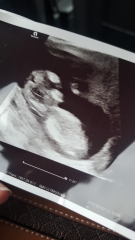

BOY OR GIRL? 12 week scan pic.

Just for fun..... take your guesses using hub theory or any other methods you know of!

I would say girl! Both nub and skull! Xx

There’s absolutely no truth in the skull theory unfortunately, skulls don’t change until adolescence. Nub theory can be accurate if you have a clear picture, most accurate after 12+4 so you’re still a bit early. Leaning towards girl though.

Thankyou- yes I think I'm seeing a more girly nub

i would go girl... we've just become grandparents to one boy and have another boy due fairly soon and their heads on their scans do look different to yours... but when i compare the scans of our two they look the same